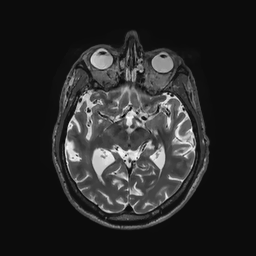

Multi-modality (or multi-channel) imaging is becoming increasingly important and more widely available, e.g. hyperspectral imaging in remote sensing, spectral CT in material sciences as well as multi-contrast MRI and PET-MR in medicine. Research in the last decades resulted in a plethora of mathematical methods to combine data from several modalities. State-of-the-art methods, often formulated as variational regularization, have shown to significantly improve image reconstruction both quantitatively and qualitatively. Almost all of these models rely on the assumption that the modalities are perfectly registered, which is not the case in most real world applications. We propose a variational framework which jointly performs reconstruction and registration, thereby overcoming this hurdle. Numerical results on simulated and real data show the potential of the proposed strategy for various applications in multi-contrast MRI, PET-MR, and hyperspectral imaging: typical misalignments between modalities such as rotations, translations, zooms can be effectively corrected during the reconstruction process. Therefore the proposed framework allows the robust exploitation of shared information across multiple modalities under real conditions.